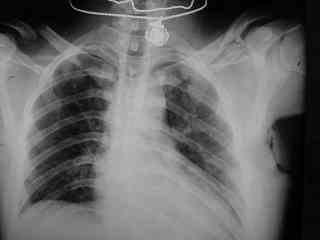

C> Postupil ko mne bolnoi s perelomom obeih kluchits, neznachitelny

C> pneumotorakx sleva.

Накостный остосинтез обех ключиц в одну сессию рекон.пластиной в условиях интубационного наркоза с положительным ПДКВ (+ 5-7 мм вод. ст.) и интраоперационным контролем степени пневмоторакса. Возможно, дренирование плевральной полости слева, по результату рентгенконтроля, по Бюлау.

Справа перелом практически поперечный, можно попробовать интрамедуллярно стержнем. Личного опыта правда не имею, у нас стандартом при оперативном лечении переломов ключицы является тот же остеосинтез пластиной. Но в литературе описана методика даже закрытого остеосинтеза - так, в порядке обсуждения.

Bolnogo operirovali plastinami, snimky zdes'.

CIMG1145.JPG

Похоже, все прошло по плану. Поздравляю с успешной операцией!